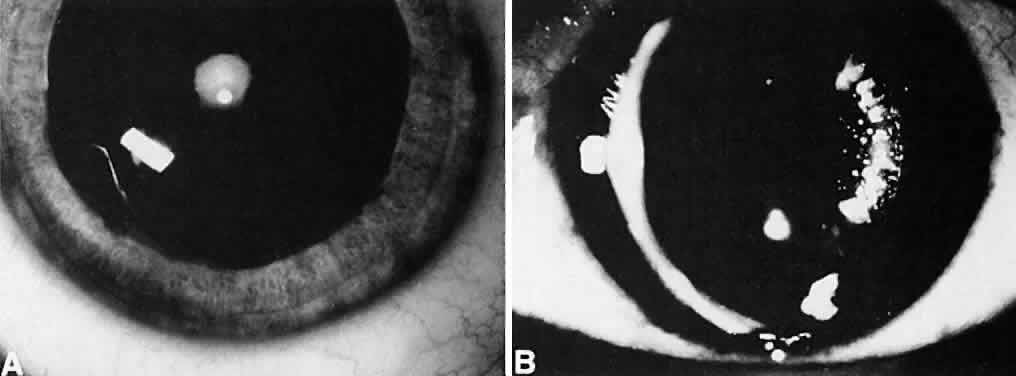

Not all cataracts require surgical treatment. Eyes with punctate or small anterior polar cataracts and others with partial opacification of the lens, such as posterior lenticonus, which only slightly interferes with the refraction of light, are best followed and not surgically treated (Fig. 1). In some cases, it is difficult to determine whether the presence of a partial cataract is responsible for a decrease in visual acuity or whether the refractive error or optical distortion produced by the cataract has produced a mild, reversible form of deprivation amblyopia. In these situations, correction of the refractive error and a trial of occlusion therapy should be attempted. If the visual acuity improves, it may be deduced that amblyopia was responsible for the loss of visual acuity and that the optical distortion produced by the partial cataract is not yet surgically significant.

Usually, anterior polar cataracts are visually insignificant and allow normal visual development (see Fig. 1). However, some affect vision, and all require careful monitoring.7 Centrally located cataracts that are on or near the posterior lens capsule have a greater effect on the refraction of light and visual acuity (Fig. 2). Nuclear cataracts associated with metabolic disorders or prenatal infections produce double refracting systems that cause optical distortion and significantly decrease visual acuity (Fig. 3).